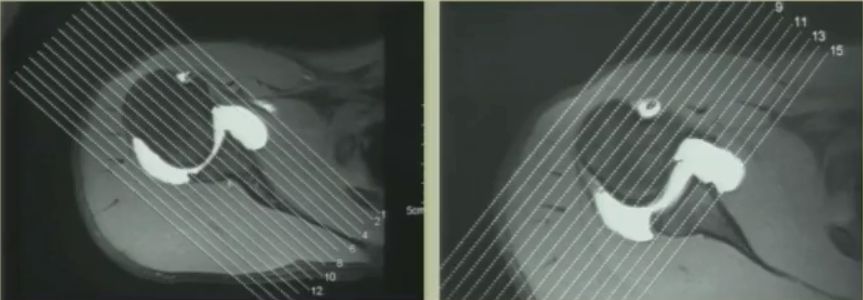

重点 重点一:肩袖的解剖特点 肩袖是包绕在肱骨头周围的一组肌腱复合体,形成一个类似于“袖口”状的结构,如图1所示。前方为肩胛下肌腱,上方为冈上肌腱,后方为冈下肌腱和小圆肌腱,这些肌腱将肱骨头稳定于肩胛盂上,对维持肩关节的稳定和肩关节活动起着极其重要的作用。 图1 肩袖解剖示意图 重点二:肩袖的力偶结构 肩袖的运动功能主要通过两对力偶完成:肩胛下肌VS冈下肌、小圆肌;冈上肌VS三角肌。 ??(1)肩胛下肌VS冈下肌、小圆肌 肩关节前方的肩胛下肌与后方的冈下肌、小圆肌形成一对力偶(如图2所示),该力偶能够将肱骨头固定于肩胛盂上,维持肩关节的稳定性,同时可以完成肩关节的旋前与旋后运动。 图2 力偶-肩胛下肌VS冈下肌、小圆肌 ??(2)冈上肌VS三角肌 单纯依靠三角肌的外展提拉作用,无法完成肩关节外展运动。冈上肌的作用力有向下方向的垂直分解力(如图3所示),该力能够下压肱骨头,为肩关节外展提供支点,使得肱骨能够围绕该支点完成外展运动。 图3 力偶-冈上肌VS三角肌 重点三:肩袖损伤的机制 肩袖损伤机制可分为两大类:第一类是有明确的外伤史导致肩袖发生急性撕裂;第二类是慢性退变性改变,此类临床最为常见。下面重点介绍慢性退变性肩袖损伤的发病机制。 肩关节前屈、外展时,肱骨大结节与肩峰前三分之一、喙肩韧带和肩锁关节发生撞击,导致肩峰下滑囊炎等退变性改变,日积月累逐渐发展为肩袖撕裂。 根据此理论可以对肩峰形态进行划分,拍摄肩胛骨Y位影像(如图4所示): I型肩峰下表面平滑; II型肩峰下表面为弧形; III型为钩形肩峰。 在肩峰撞击这一始动因素下,随着患者年龄增长,肩袖组织退变,日常上肢上举动作过多等导致肩峰撞击次数增多,最终导致肩袖损伤。 图4 肩峰形态分型 重点四:肩袖损伤的临床表现 外伤导致肩袖撕裂的患者一般均有明确的外伤史。而慢性退变性肩袖损伤的患者,其年龄较大,多为劳损性退变导致的损伤,患者肩关节功能障碍及疼痛症状一般持续时间较久。患者最典型的两个临床表现是“疼痛”+“力弱”。患者主诉肩关节疼痛剧烈,疼痛区域集中在肩峰前外缘、肱骨大结节区域。患者力量减弱同时表现为耐力较差,如无法长时间维持上肢上举动作等。 重点五:肩袖损伤的体格检查 ??(1)疼痛弧 疼痛弧是肩袖损伤患者的临床表现之一。患者肩关节外展至60-120°时会出现明显疼痛表现,继续外展超过这一角度范围时,疼痛消失(如图5所示)。出现该表现的原因是,在肩关节外展至60-120°范围时,肱骨大结节与肩峰发生撞击产生疼痛,继续外展超过这一角度范围时,肱骨大结节不再与肩峰发生接触,疼痛消失。 图5 疼痛弧示意图 ??(2)Neer征 检查者一手固定肩胛骨,另一手保持肩关节内旋位,使患者拇指尖向下,然后使患肩前屈过顶,如果诱发疼痛,即为阳性(如图6所示),机理是人为的使肱骨大结节与肩峰前下缘发生撞击,从而诱发疼痛。 图6 Neer征 ??(3)冈上肌抗阻试验-Jobe’s试验 上肢外展90°前屈30°拇指向下,上肢位于肩胛骨水平,类似于倒水杯动作(如图7所示),故该试验又名空杯试验,检查者用力向下按压上肢,患者抵抗,与对侧相比力量减弱或者患者出现疼痛,提示肩袖病变或者冈上肌腱病变或者撕裂。 图7 Jobe’s试验即空杯试验 ??(4)落臂征 将患者患肢被动上举,然后令其缓慢放下,如果不能慢慢放下,出现突然直落到本侧,为本试验阳性,说明冈上肌腱完全撕裂。 ??(5)外旋抗阻试验 患者肩关节处于内收位,屈肘90°,肘部处于体侧并夹紧,让患者抵抗阻力将双肩外旋(如图8所示)。如力量明显减弱即为阳性。提示冈下肌和小圆肌肌腱损伤。 图8 外旋抗阻试验 ??(6)Lift-off试验 患者将手背置于下背部手心向后,嘱患者将手抬离背部(如图9所示),检查者给予抵抗阻力,不能完成动作为阳性,提示肩胛下肌损伤。 图9 Lift-off试验 ??(7)压腹试验 患者将手置于腹部,手背向前,屈肘 90 度,肘关节向前。检查者将患者手向前拉,而嘱患者抗阻力做压腹部的动作。患者在将肘向前时不能保持手压腹的力量或肩后伸则为阳性,提示肩胛下肌损伤。 图10 压腹试验(左侧为阴性,右侧为阳性) 重点六:肩袖损伤的辅助检查 ??(1)X线检查 可见到大结节硬化,肩峰前缘骨赘囊性变,肩峰、肱骨头间隙变窄等表现(如图11所示)。 图11 肩袖损伤的X线表现 ??(2)MRI检查 进行MRI检查时,尤其要注意MRI扫描切割平面的确定,应该选择斜矢状位(垂直于肩胛骨平面)及斜冠状位(平行于肩胛骨平面)进行切割(如图12所示),这样才能完整的显示冈上肌腱、冈下肌腱。尤其要注意观察T2压脂像,该显像序列对于观察肩袖损伤最为重要。 图12 斜冠状位和斜矢状位切割 肩袖损伤的MRI表现主要有三点:①信号增高;②肌腱厚度增粗;③肌腱连续性中断。以上三条只要出现一个,就可以确定有肩袖撕裂的MRI表现(如图13所示)。 图13 肩袖撕裂的MRI表现 ??(3)CT肩关节造影检查 CT肩关节内造影检查适用于MRI检查禁忌的患者,该方法向关节腔内注入造影剂,如冈上肌腱存在全层撕裂,则表现为断裂部位造影剂充盈缺损(如图14所示)。但注意该方法只能显示肩袖全层撕裂,对于部分撕裂,则可能造成漏诊。 图14 肩关节造影示冈上肌腱断裂 重点七:肩袖损伤与肩周炎的鉴别诊断 临床诊疗中,肩袖损伤患者极易被误诊为肩周炎进行治疗。下面列举两者的鉴别诊断要点: 其中最重要的鉴别点是活动范围,肩袖撕裂患者其肩关节主动活动受限,被动不受限;而肩周炎患者其肩关节活动范围主动、被动均明显受限。尤其需要注意肩关节的外旋活动,如患者肩关节外旋活动正常,则基本可以排除肩周炎。 总结 肩袖损伤的诊断,要结合患者症状、体格检查和影像学结果进行综合诊断,一定要注意对患者肩关节主动、被动运动范围的检查,切勿将肩袖损伤误诊为肩周炎,延误治疗时机。